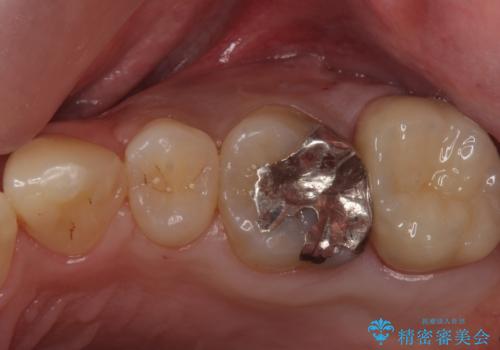

- 奥歯のザラザラが気になり、白い被せ物をしたいとのことで来院。

レントゲンや拡大鏡で確認をしたところ歯の表面は粗造になっていたが

う蝕があるわけではないので以下の提案を行った。

銀の詰め物のやりかえも検討されています。